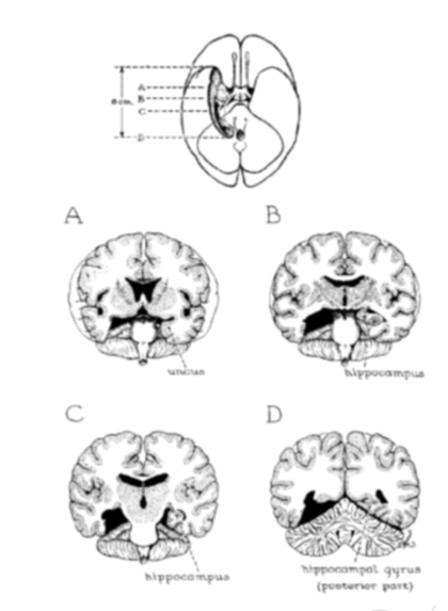

威廉向亨利推荐的手术,是一种双侧内侧颞叶切除术。威廉曾用这种技术切除了 30 例精神分裂症患者的双侧颞中叶皮质,但范围都有所区别。

其中,仅有 1 例像亨利一样要切除「双侧前三分之二的海马及海马回,以及钩回和杏仁核」,亨利也是首位仅因癫痫就接受这类手术的患者。

1953 年 8 月 25 日,亨利接受了手术。在术中 EEG 的监控下,尽管没有找到致病灶,威廉还是按照原定计划,用抽吸器小心翼翼地吸出了亨利大脑的内侧颞叶、杏仁核、沟回、内嗅皮层以及海马体。

安内瑟还通过扫描切片,获得了高分辨率的数字图像。通过 3D 图像重建大脑,在时隔多年后终于找到了威廉医生对亨利手术的确切切除范围。残留的左右侧内嗅皮层为 0.03 和 0.11 立方厘米,相当于正常体积的 1.7% 和 6.5%。据安内瑟估计,残留的海马右侧长 45.4 毫米,左侧长 47.2 毫米。

谜团似乎解开了:内嗅皮层是皮层和皮层下核之间的主要的感觉输入传输通道,双侧内嗅皮层被切除,使残留的海马后部也失去联络,从而造成了亨利严重的顺行性遗忘症。